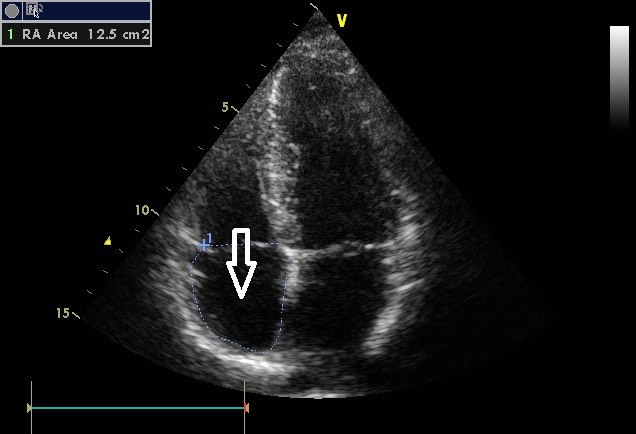

2700. Структурой, указанной стрелкой на сонограмме изображения, является